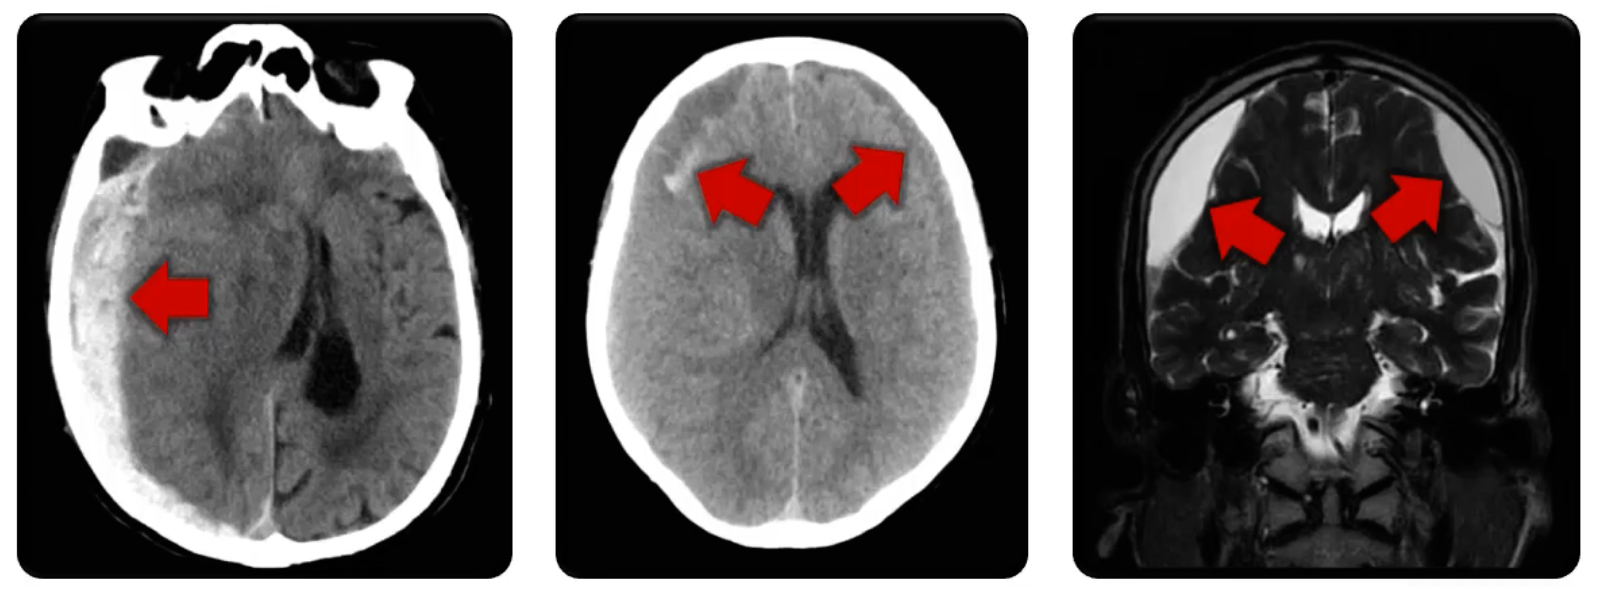

Subdural Hemorrhage

Subdural bleeding

spontaneous or trauma

Appear on the surface of the brain, may include new or coagulated blood

Subarachnoid Hemorrhage

Subarachnoid bleeding around the Circle of Willis

Caused by ruptured aneurysm

Subarachnoid Hem.